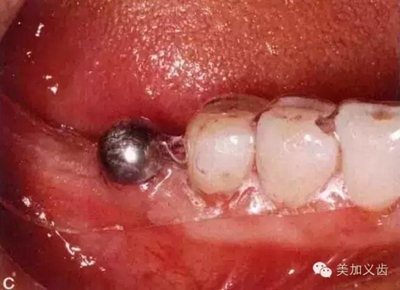

種植牙過程中,除了拍片是醫(yī)生們一項重要的工作,使用的材料也是非常重要的因素:

美加個性化種植基臺是通過計算機設(shè)計,高精密CAD/CAM五軸機床銑削而制造出來,為患者量身定做的種植牙基臺。它全面兼容國際各大品牌種植系統(tǒng),提供氧化鋯、純鈦材質(zhì)及定制化服務(wù)。

來源:美加義齒